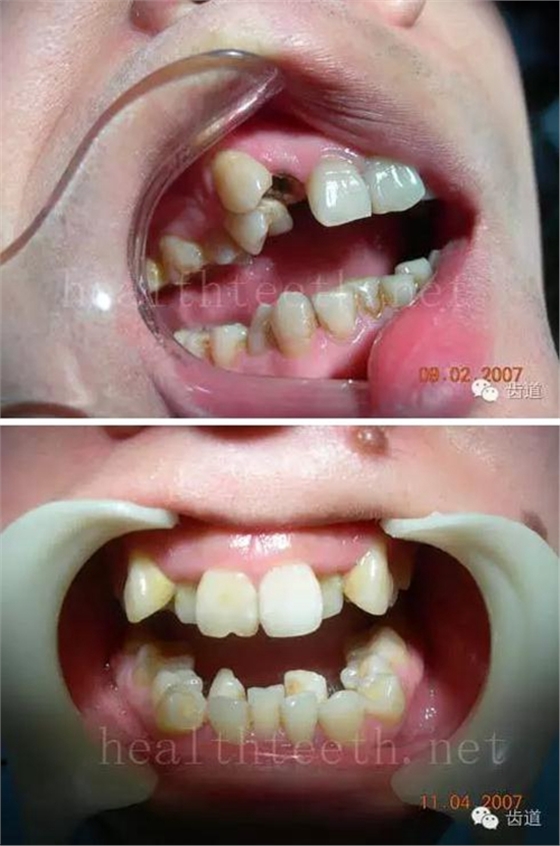

12歲孩子門牙的齲齒